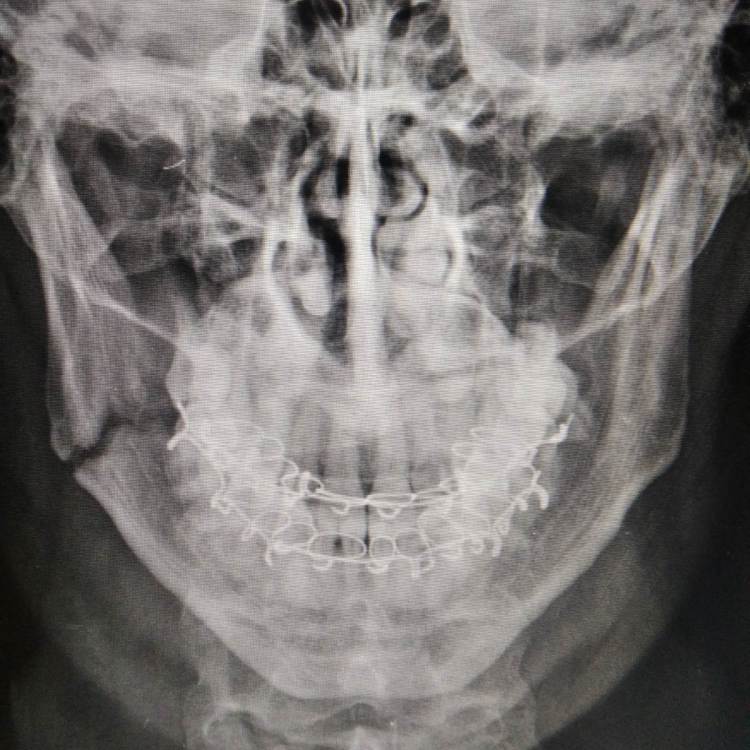

Russ Опубликовано 16 августа, 2022 Поделиться Опубликовано 16 августа, 2022 Доброго времени суток, Уважаемые специалисты и посетители форума. Очень нужна Ваша помощь. 6 недель назад получил закрытый перелом челюсти справа со смещением. Зуб мудрости удалили, зашинировали, ожидании операции провел неделю в стационаре , но был выписан, сказали "так сростется". Загрузил фото рентгена (10 дней после наложения шин) и фото КТ (6 недель). Бежать заново ломать, пока не схватилось до конца все? Заранее спасибо. Ссылка на комментарий

kramer Опубликовано 17 августа, 2022 Поделиться Опубликовано 17 августа, 2022 Отломки явно не на своем месте. Надо делать остеосинтез. 1 1 2 Ссылка на комментарий